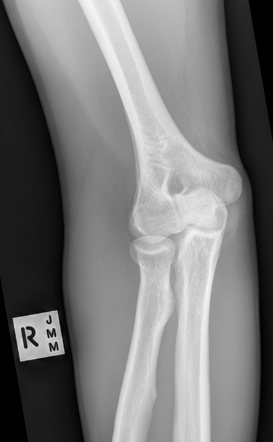

AP Elbow